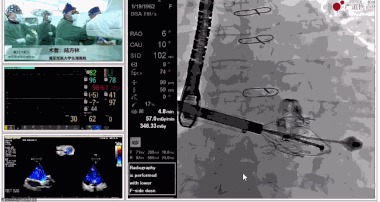

▲瓣膜植入后釋放的過(guò)程

▲瓣膜植入后三維超聲影像

▲瓣膜植入后右心室造影

在手術(shù)直播中瓣膜植入過(guò)程不到10分鐘,手術(shù)獲得圓滿(mǎn)成功,充分體現(xiàn)徐志云、陸方林團(tuán)隊(duì)技術(shù)精湛,團(tuán)隊(duì)協(xié)作默契及器械的優(yōu)越性。